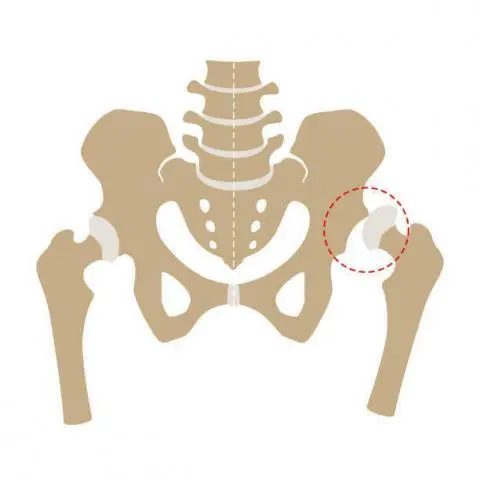

Doğuştan Kalça Çıkığı Nedir?

Doğuştan kalça çıkıklıkları, tedavi edilmediğinde ilerleyen yaşlarda ciddi problemlere neden olabilen bir durum olduğu için doğum sonrasında kontrol ve tedavi son derece önemlidir. Bu noktada doğum sonrasında yapılan kalça ultrasonu ile kalça çıkığının olup olmadığı mutlaka tespit edilmelidir. Doğuştan kalça çıkığı, tam çıkık ya da kısmi çıkık şeklinde görülebilmektedir. Eğer kalça çıkığı tespit edilirse, çıkığın … Continue reading